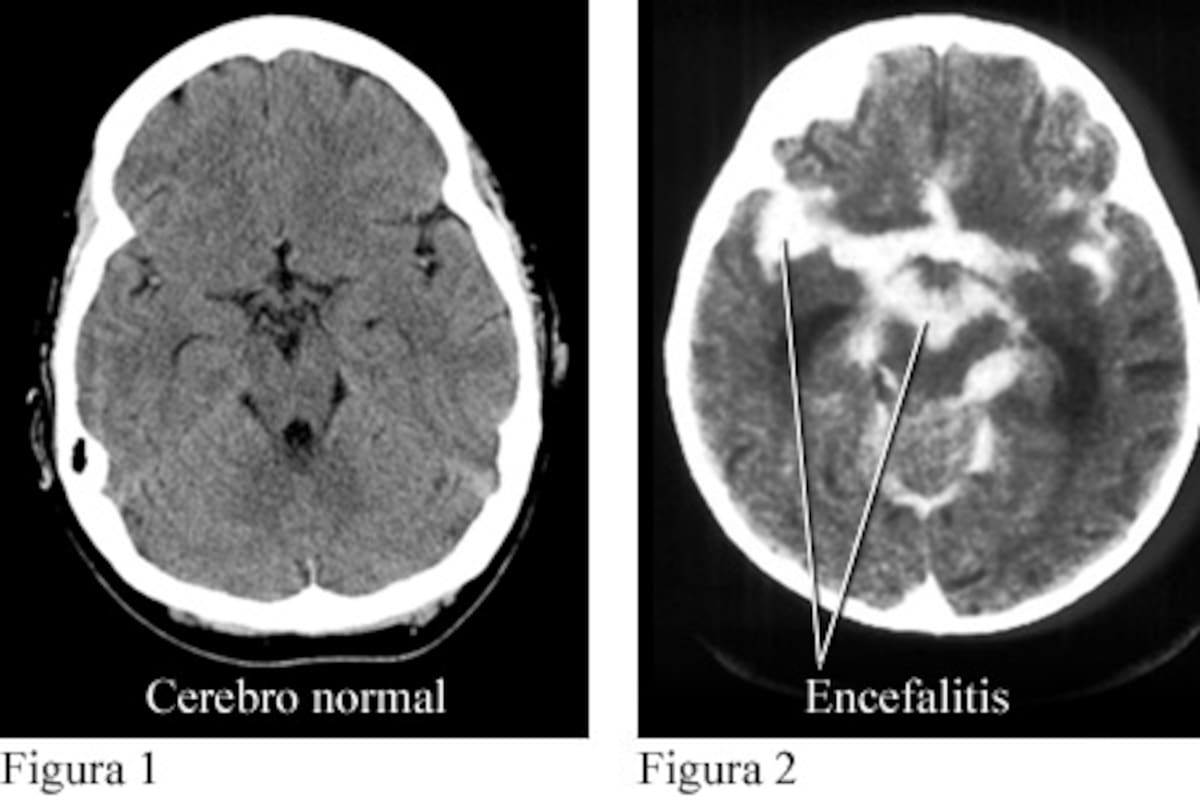

Día Mundial de la Encefalitis: Información y Concienciación sobre una Enfermedad Grave

México.- Cada 22 de febrero se conmemora el Día Mundial de la Encefalitis, una fecha establecida desde 2014 por la Sociedad de Encefalitis (Encephalitis Society) con el objetivo de informar y concienciar sobre esta enfermedad, que consiste en la inflamación de las estructuras cerebrales.